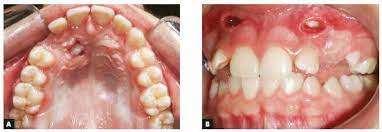

Open eruption through a window; If the crown is positioned mesial to the lateral incisor, a closed technique for the pataltal eruption of canine. Dr kokich recommends open and preorthodontic exposure of palatally impacted canines. Management of unerupted maxillary incisors 6 5.4 incisor removal 5.5 ankylosed maxillary incisors. The postoperative recovery was longer after open eruption than close eruption technique (p = 0.000). Closed eruption technique for surgical exposure 3 surgical approach can be used 1. The closed technique and the open technique. Dr vanarsdall recommends open exposure with a repositioned gingival flap (pediculated connective tissue graft) above the impacted canine. Patients perception of recovery after exposure of impacted teeth: This facilitates eruption and orthodontic traction. An attachment may be placed during or after the procedure. The present study provides information to patients and clinicians. If a canine is associated with severe resorption of the root of the incisor, an open exposure is not indicated since it endangers the vitality and existence of the incisor.

Interventions for promoting the eruption of palatally displaced permanent. If the crown is positioned mesial to the lateral incisor, a closed technique for the pataltal eruption of canine. Dr kokich recommends open and preorthodontic exposure of palatally impacted canines. Despite the unconcealed allocation, the outcome duration of canine's eruption is probably in low risk of bias as the protocol of open and closed technique is mentioned clearly, any possible confounders (age, depth of impaction) have similar distribution at baseline among groups and the definition of eruption is objective. (1) window technique, (2) full flap open procedure, and (3) apically repositioned flap technique.

Chaushu s(1), becker a, zeltser r, vasker n, chaushu g. Preorthodontic exposure and autonomous eruption The open exposure technique consists of surgical removal of the tissue covering the tooth, leaving it exposed to the oral cavity. Given the reported success of forced eruption, the technique requires… continue reading The present study provides information to patients and clinicians. Duration of surgical procedure (in min) click here to view Dr vanarsdall recommends open exposure with a repositioned gingival flap (pediculated connective tissue graft) above the impacted canine. Apically position flap the goal is to choose a technique that exposes the canine within the a zone of keratinized mucosa without involvement of the cementoenamel junction 27. The open eruption technique may be performed in two different ways, as described below. If the canine crown is positioned distal to the mesial aspect of the lateral incisor, an open technique is performed. Forced eruption can preserve the natural root system and related periodontal architecture, resulting in years of additional service for the patient. Open eruption through a window; In this technique sufficient space.

If the canine crown is positioned distal to the mesial aspect of the lateral incisor, an open technique is performed open'er. (1) window technique, (2) full flap open procedure, and (3) apically repositioned flap technique.